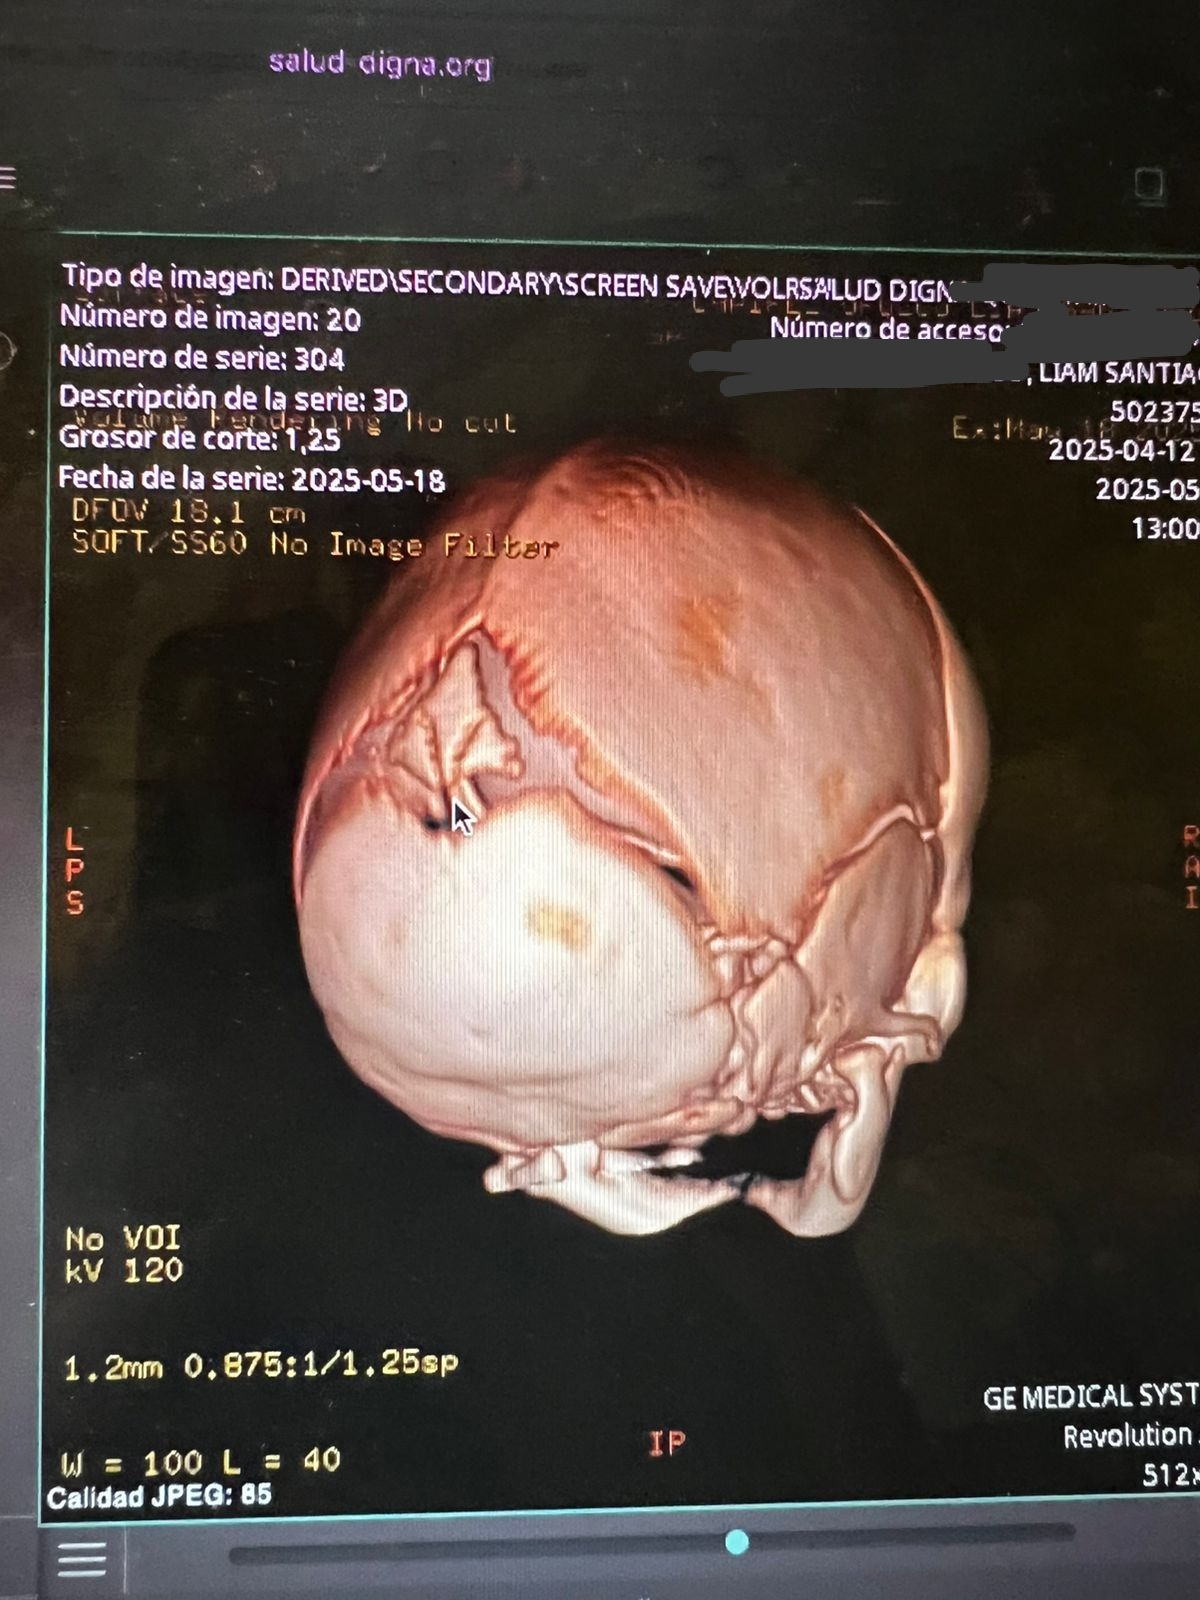

Hola mi nombre es Diana y hace aproximadamente un mes nació mi sobrino Santiago, ayer le acaban de detectar craneosinostosis y es necesario realizarle una cirugía en su cabecita lo más rápido posible para que su cerebro pueda tener un desarrollo adecuado, para realizar esta cirugía en los hospitales públicos hay lista de espera de seis meses aproximadamente y debido a la urgencia y que vamos contra reloj ya que se debe realizar en los primeros meses de vida que es cuando es menos riesgosa la operación por eso la única opción que nos queda es realizarla en un hospital privado por eso el costo tan elevado, les pido de todo corazón su ayuda cualquier aportación es de gran ayuda para poder juntar el dinero cuanto antes y el pequeño Santi pueda ser operado cuanto antes.

Liam Santiago